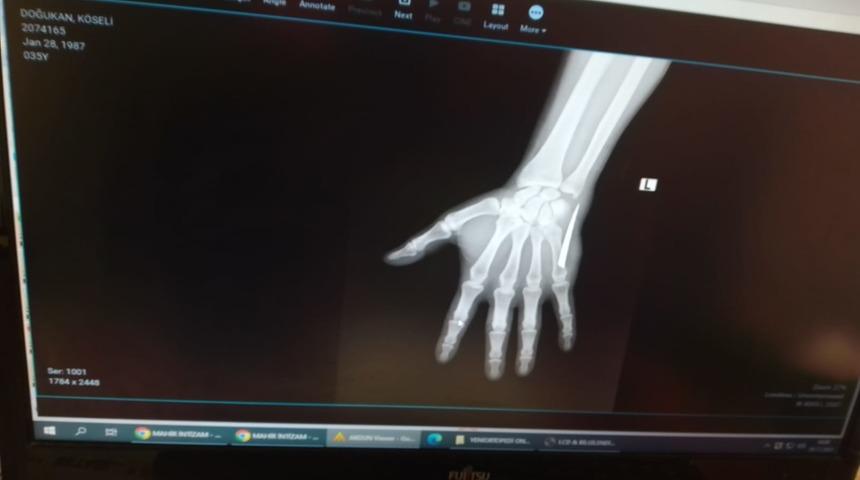

Doğukan Köseli, gazetecilere, yaşanan olay sonrası Devrek Devlet Hastanesi'ne gittiklerini belirterek, röntgen işlemi yapılmadan eline zımba dikiş atıldığını öne sürdü. Köseli, daha sonra elindeki ağrıların arttığını anlatarak, "Bir baktım parça gibi bir şey vardı. Kontrol ettiğimde sert bir cisim vardı. Bir baktık bıçak parçası vardı, çıkartmaya çalıştık, çıkartamadık, büyük olduğunu fark ettik. Aynı hastaneye gitme konusunda kararsız kaldık. Çaycuma Devlet Hastanesine gittik. Orada film çektiler, küçük bir parça sanıyorduk, epey bir büyükmüş. Doktor, bunun ameliyatla alınması gerektiğini söyledi. Şu an sağlık durumum biraz iyi ama parmağımda uyuşma var hala." dedi.